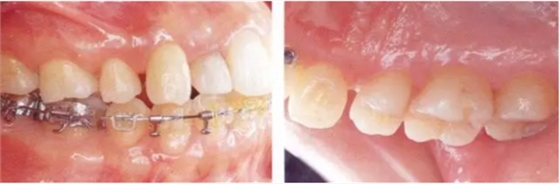

22222222222222222222222222222222222.png

▲圖19-5,6

▲圖19-5 初期治療完成后的狀態(tài),炎癥得到了很好的控制。

▲圖19-6 在下頜右側(cè)磨牙部植入種植體恢復(fù)垂直高度以及形成支抗點(diǎn),開始正畸治療。